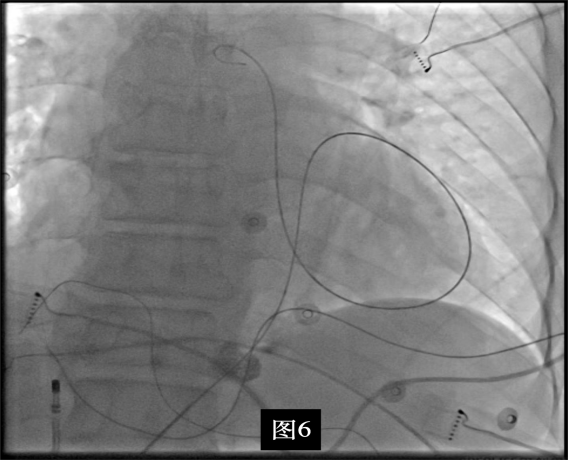

手术中,周明礼团队凭借其丰富的临床经验和精湛的技术,穿刺右股动脉后,将消融大头顺利送入主动脉,于主动脉瓣上标测到最早点(图3红色点)领先体表8ms,电位不理想,果断去到主动脉瓣下左室穹顶部标测,标测到最早点(图4白色点)领先体表25ms,放电消融3s,早搏消失,消融90s后观察2min后,早搏恢复,在该有效点周边补充消融,早搏依旧未能消失,考虑起源点较深,内膜消融未能透壁损伤到起源,随

即穿刺股静脉,将消融大头送至冠状窦内,在GCV远端对应位置标测到最早点(图5绿色点)领先体表27ms,消融后早搏未能消失,周明礼评估起源点偏心外膜,能量依旧不能穿透损伤到起源点,内膜消融基本无效后,果断选择难度系数最为复杂的干性心包穿刺心外膜消融。在导丝的指引下,将消融大头送至心包层(图6),于外膜标测到靶点(图7黄色点)电位领先体表31ms,单极电位无r波且有顿挫,ssummit外膜离冠状动脉较近,比较危险,保证安全,进行了冠脉造影(图7),显示距离LAD和LCx有一定距离,相对安全,随即放电,2s室早消失,10s患者出现心率变慢,该区域走形迷走神经节,消融导致心率减慢,随后保证心率正常的情况下,消融够60s,随后观察半小时,早搏没有恢复,手术成功(图8)。经过不懈的努力,患者恢复了窦率,心脏功能也逐渐恢复正常,手术取得了圆满成功。